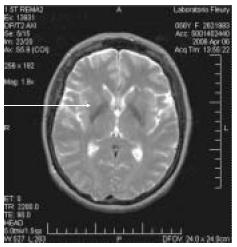

Paciente com 58 anos iniciou quadro de progressiva oligocinesia e rigidez no dimídio esquerdo, sem praticamente apresentar tremor. Foi submetida a uma série de tratamentos com drogas antiparkinsonianas, sem sucesso (levodopa, amantadina, bipirideno, pramipexole). Ao mesmo tempo começou a apresentar mudança de coloração da mão esquerda e infiltração edematosa dessa mão. Sua ressonância nuclear magnética de crânio mostrou diminuição do volume do putamen no lado direito e, nas seqüências ponderadas em T2, hipointensidade de sinal no putamen e hiperintensidade linear na região postero- lateral (também vista nos cortes com densidade de prótons). Do ponto de vista anátomo-patológico, pode-se esperar, nesse caso, a presença de